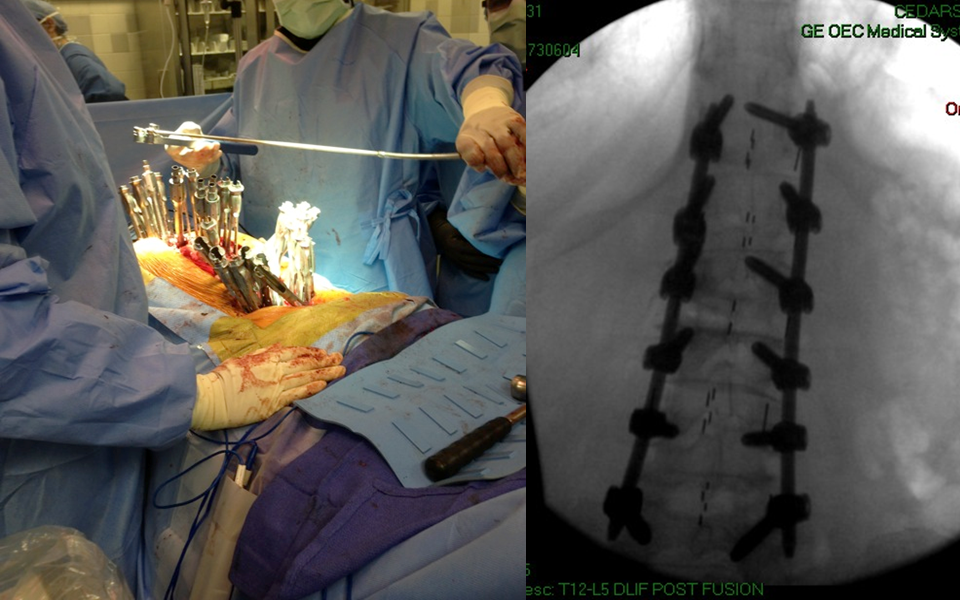

在微创脊柱外科热潮汹涌而至的当下,腰椎退变性疾病的治疗快要达到“无微不至”的程度。那么,就脊柱领域难度超高、风险性巨大的退变性脊柱侧凸而言,医生如何选择开放或微创技术,成为目前脊柱外科的热点之一。

陆军总医院、全军骨科研究所李放教授分析了国内外相关研究,并结合临床经验得出结论:开放手术能够获得更好的矫形和减压效果;微创技术作为脊柱医生手中的新武器,对于一部分畸形较轻的病例,微创技术可以发挥其优势,但要严防特殊并发症;对于畸形严重的病例,微创手术处理存在困难,可谓开放能及微创所不及。他认为,开放和微创技术应该有机结合,重要的是如何去选择适应证,对不同的病例制订个体化方案。